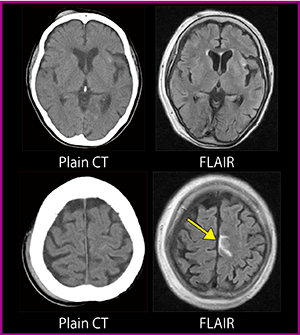

画像診断においては,脳出血はCT,脳梗塞はMRIの拡散強調画像というのが定番となっている。しかし,CTでもわからないようなわずかな出血が,FLAIR画像で高信号に示されることがある。図4は,0.4TオープンMRIで撮像した外傷性出血症例(70歳代,女性)だが,特に脳溝に近い部位の微小な出血では,FLAIR画像が有用であると考えている。

図4 外傷性出血(70歳代,女性,0.4T)